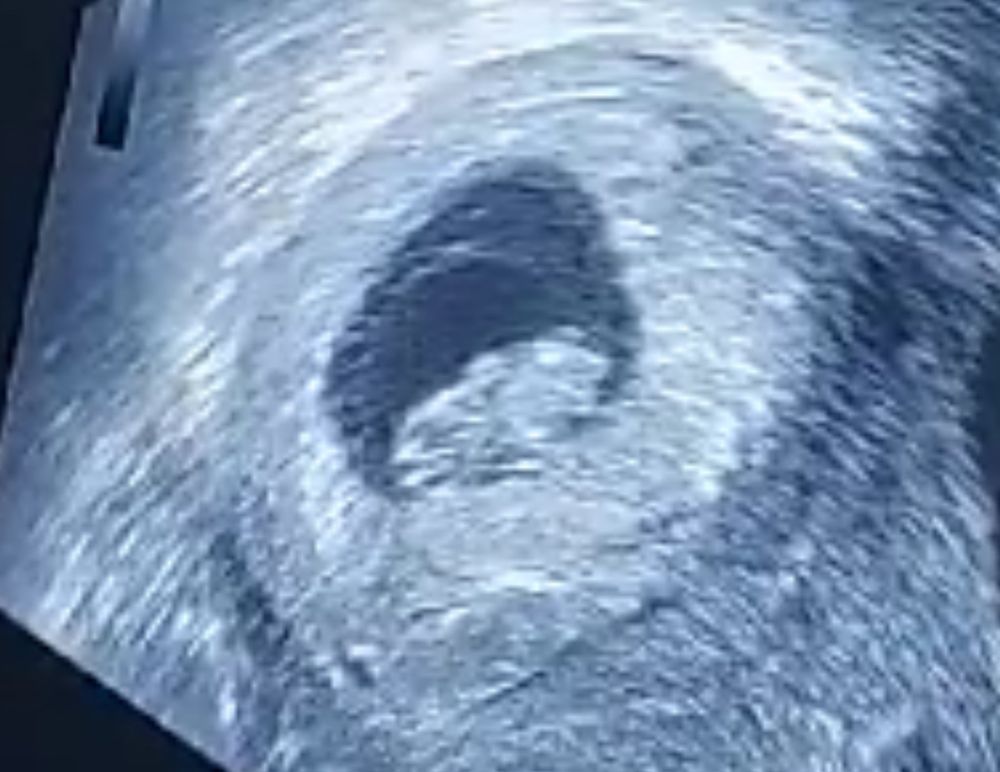

Очередное свидание. 9 недель

а сегодня наш человек аж 2.2 см. Уже посмотрели отростки ручек и ножек, и хвост🤣🤣🤣 ну копчик будущий. Какое это волшебное ощущение. Все у нас пока хорошо, все по сроку. Подросли как надо с прошлого узи. Отслоек/угроз нет. И пусть так будет и дальше. Ляльчонок продолжает мучить маму токсикозом, но все терпимо. Все, как должен быть. Потерпим.